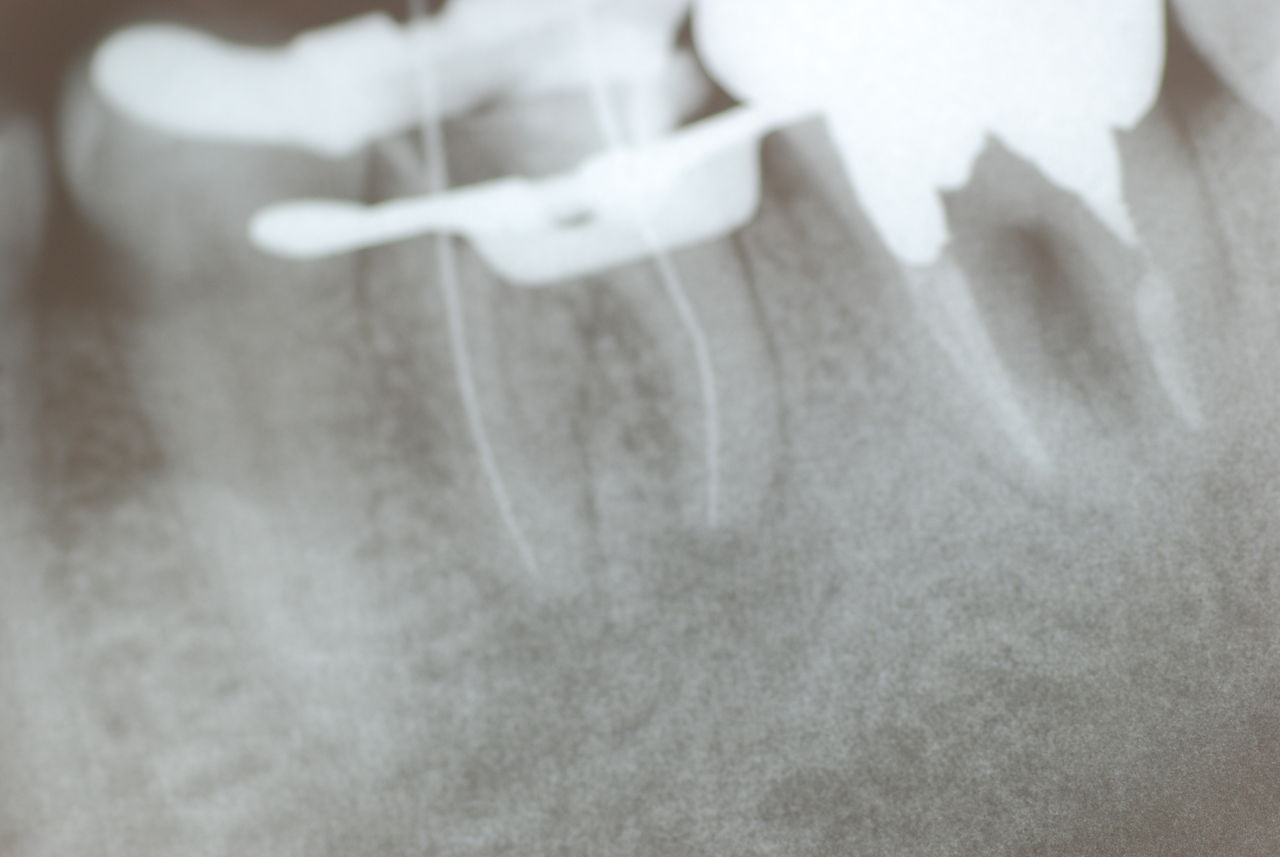

そして一番知りたかった歯周病や歯牙の根尖病巣と体の感染症についても質問しました。

明確な答えに唖然といたしました。

歯周病と根尖病巣(根管内とは違う)の菌は同じだとか、所謂biofilm感染症なのだと。

だから血管に入り込むと血液中にウロウロしてどこかの内皮細胞に住み着き、ここで

血液中からは居なくなる。(だから血液培養はこの時点で意味がなくなる。抗生剤使用も

意味なくなるのではないでしょうか)そして

やがて白血球や単球(細胞内ではmacro phageと名前が変わる。)で貪食される。

ところがこの時に血管は硬化を起こすのだとか、動脈硬化の理由等初めて知りました。

すべて合理的な体の反応なんですね。だから感染症による菌血漿は注意が必要なんですね。